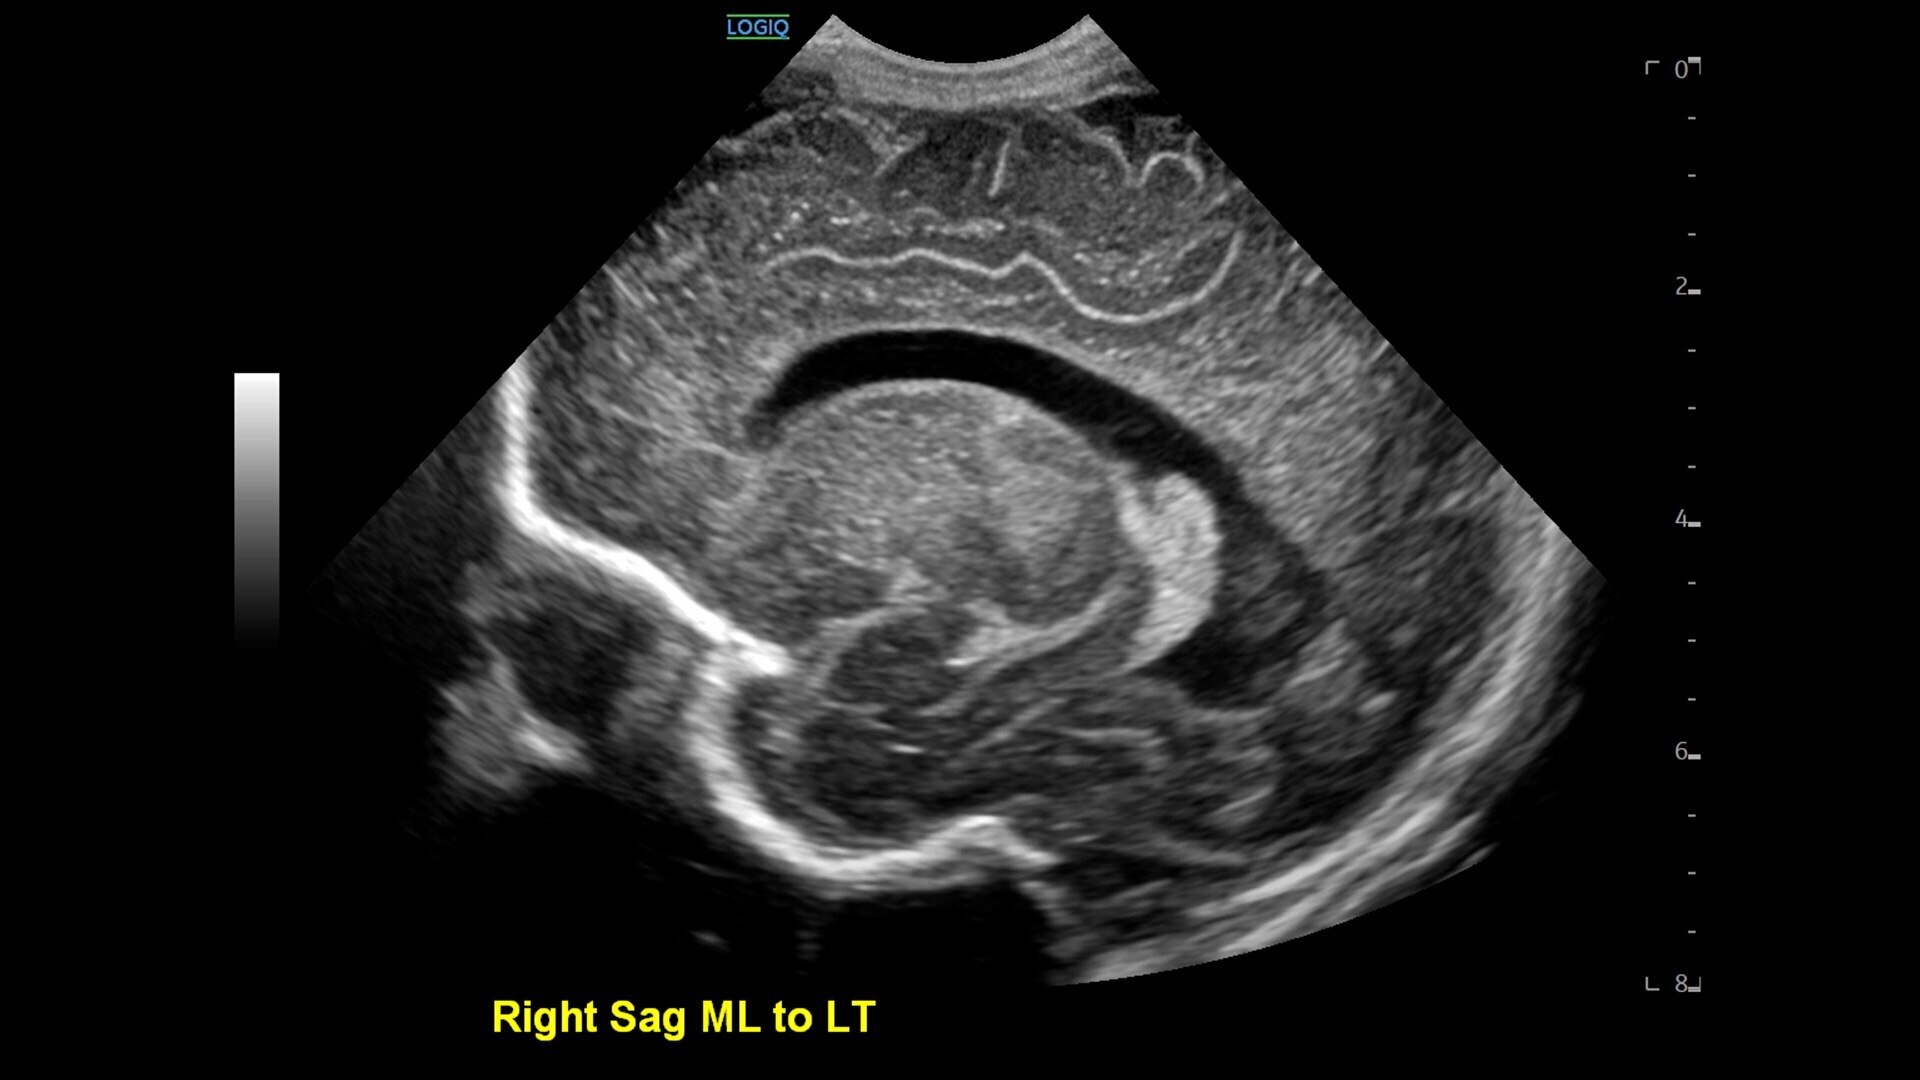

• New Auto Renal Measure Assistant: Automatically detects kidney and measures length, height and width in seconds*

• New SmartEdit: Shortcut keys enable segmentation-based editing capabilities in auto measurement tools, assisted by AI-based anatomy detection